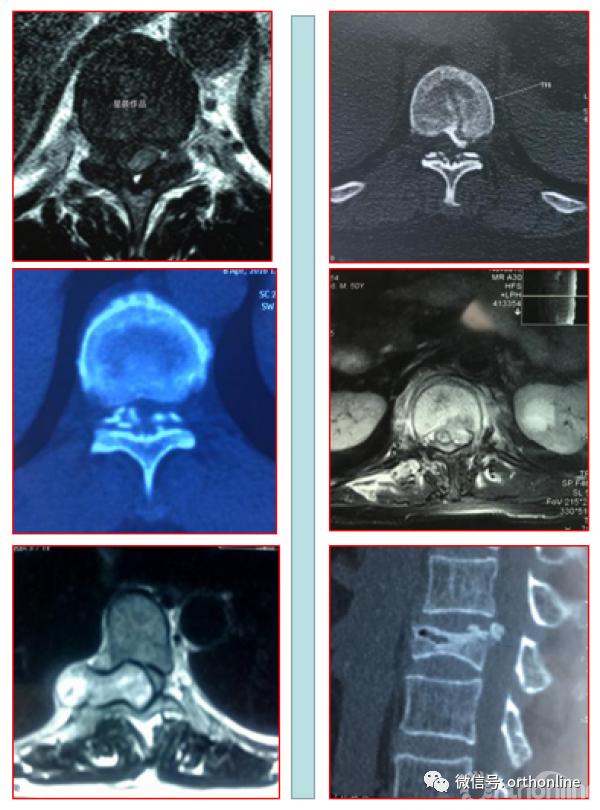

脊柱内镜手术通常作为首选手术方法,能有效地减压并进行相应的处理。适用于胸椎管狭窄症,如胸椎黄韧带肥厚症、胸椎间盘突出症、胸椎后纵韧带骨化症等,尤其适合单节段狭窄者。

1.胸椎结核:在脊柱内镜下进行穿刺及置管引流等;

2.胸椎椎管内囊肿:在脊柱内镜下进行病病灶切除术等;

3.胸椎后纵韧带骨化、骨水泥渗漏等;